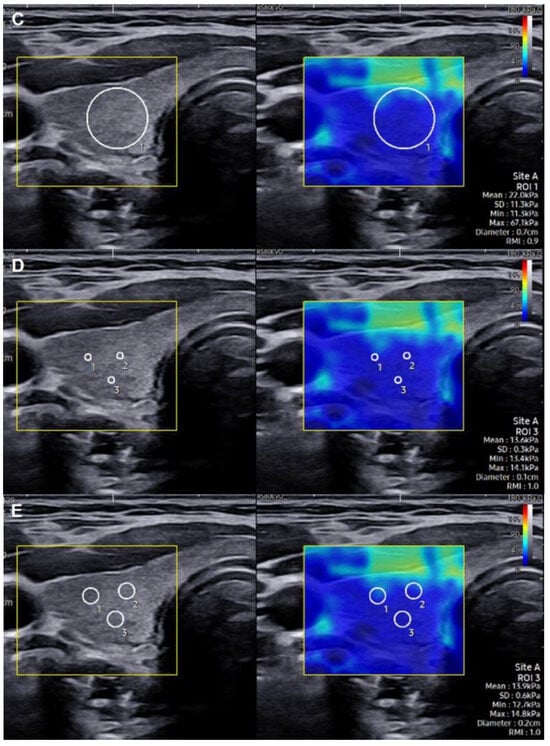

2.2. SWE Evaluation and Measurement